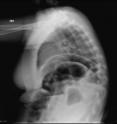

With the aim of producing high-quality X-rays with minimal radiation exposure, particularly in children, researchers have developed a new approach to imaging patients. Surprisingly, the new technology isn't a high-tech, high-dollar piece of machinery. Rather, it's based on the Xbox gaming system. Using proprietary software developed for the Microsoft Kinect system, researchers at Washington University School of Medicine in St. Louis have adapted hands-free technology used for the popular Xbox system to aid radiographers when taking X-rays.

The software coupled with the Kinect system can measure thickness of body parts and check for motion, positioning and the X-ray field of view immediately before imaging, said Steven Don, MD, associate professor of radiology at the university's Mallinckrodt Institute of Radiology. Real-time monitoring alerts technologists to factors that could compromise image quality. For example, "movement during an X-ray requires retakes, thereby increasing radiation exposure," Don said.

The technology could benefit all patients but particularly children because of their sensitivity to radiation and greater variation in body sizes, which can range from premature infants to adult-sized teenagers. Setting appropriate X-ray techniques to minimize radiation exposure depends on the thickness of the body part being imaged. High-quality X-rays are critical in determining diagnoses and treatment plans.

"To achieve the best image quality while minimizing radiation exposure, X-ray technique needs to be based on body-part thickness," Don said. The gaming software has an infrared sensor to measure body-part thickness automatically without patient contact.